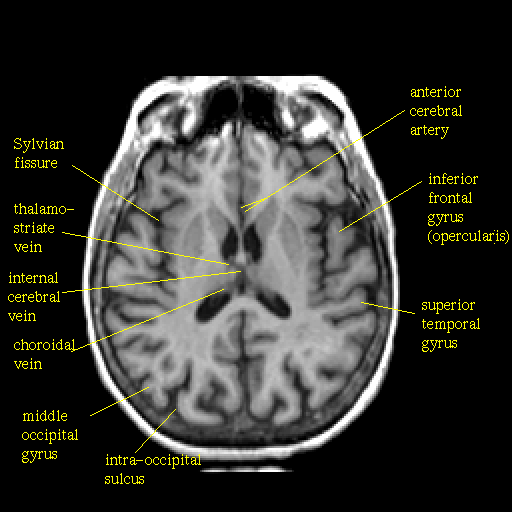

T1-weighted structural MR: Slice 30

Slice 30